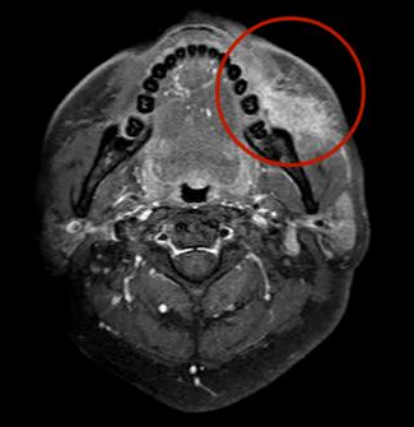

新辅助治疗后的磁共振影像,显示肿物缩小至硬币大小,累及程度减轻,左侧颊肌、咬肌强化影较前减轻。